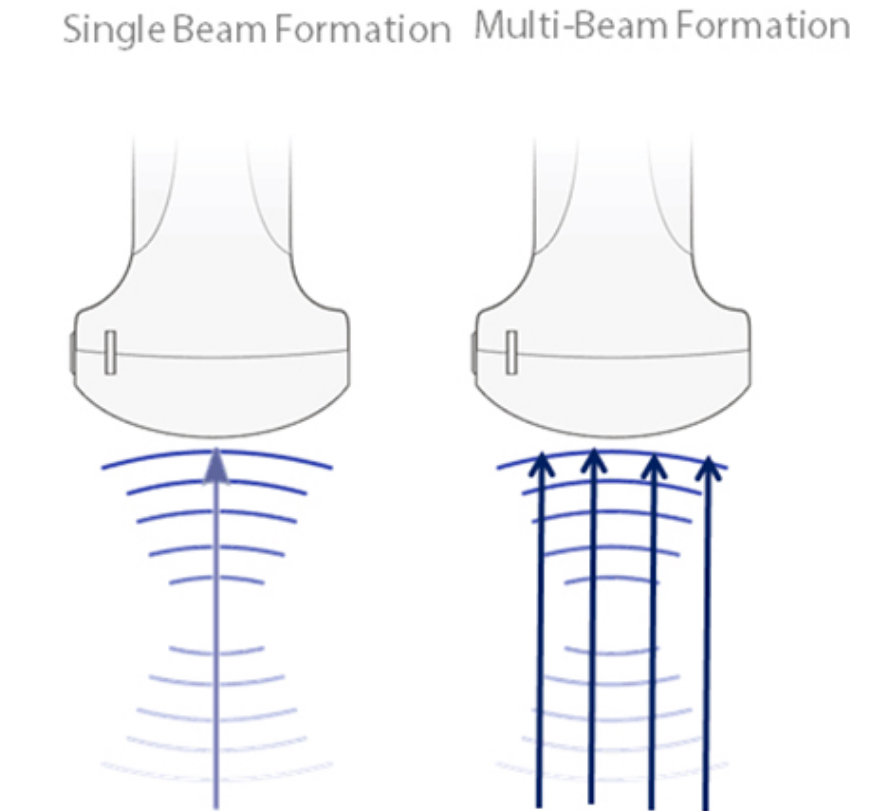

FormaciĂłn de haces mĂșltiples

UtilizaciĂłn mĂĄxima de 4?veces por haz transmitido, lo que da como resultado una mayor velocidad de cuadros y una excelente resoluciĂłn temporal.